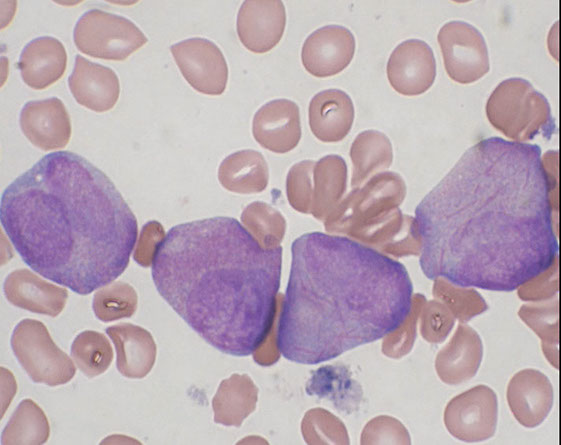

- absensce of the specific cytogenetics abnormalities seen in AML with recurrent genetic abnormalities

MC in elderly

Usually have severe pancytopenia

May appear de novo or from an evolving MDS

________________________________

IHC: w chr 5/7 del get (+) CD34, 7, TdT

________________________________

Genes: del -5 and del -7 are MC

- If NPM1 mutation identified, diagnose as AML with NPM1 mutation (despite MLD)